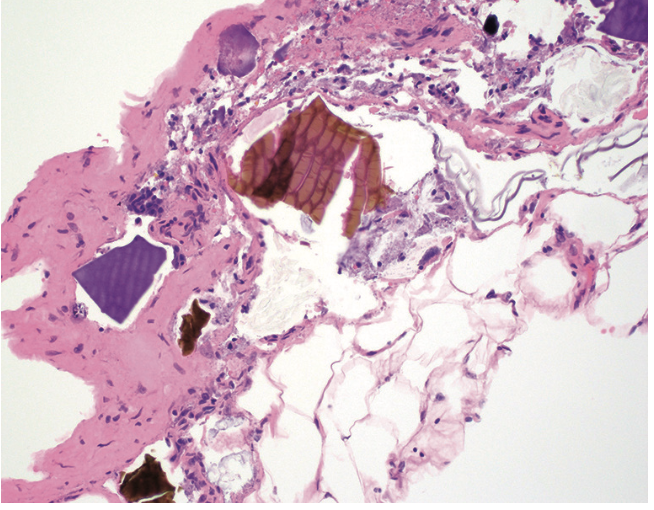

lipodistrophie du chorion (photo)